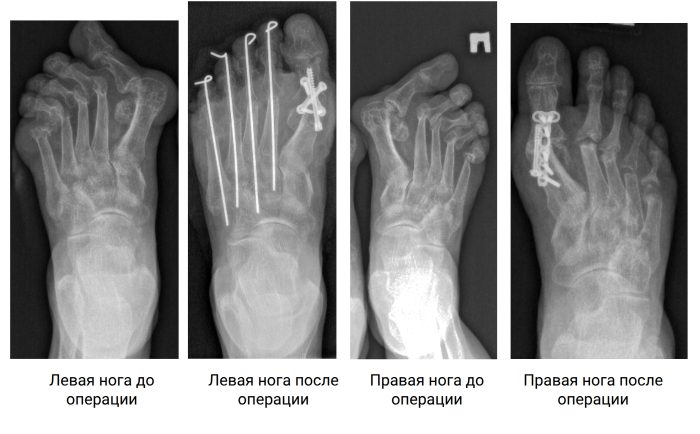

Однако лечение коллег было консервативным и не сильно помогало. Из-за этого Елена даже получила вторую специализацию по ревматологии и лучше разобралась в своем недуге. Когда стало совсем больно ходить, она обратилась в НИИТО, где в 2025 году приступили к серии сложных операций. На обеих стопах была деформация пяти пальцев с разрушением головок плюсневых костей. Сохранить суставы было невозможно. Хирурги выполнили резекцию головок 2-5 плюсневых костей, вправили вывихи малых пальцев и зафиксировали спицами.

«Малые пальцы были в состоянии вывиха, и пациентка испытывала постоянный дискомфорт, давление. Мы убрали разрушенные давящие головки плюсневых костей, тем самым добились снижения напряжения на тканях. Пальцы встают в правильное анатомичное положение, уходит подошвенное давление», — объяснил хирург-ортопед Новосибирского НИИТО Матвей Лучшев.